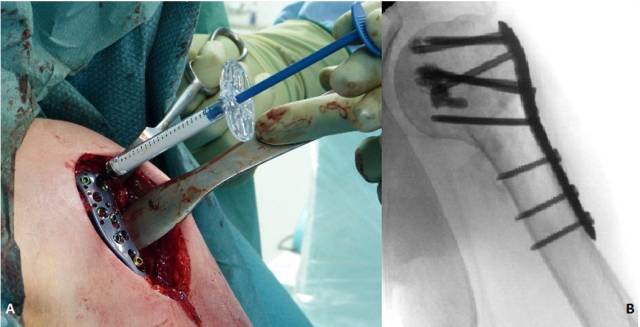

骨水泥加强固定已经成功运用于肱骨近端骨折的处理上。磷酸钙和硫酸钙骨水泥均可用在肱骨近端骨折时填充于骨折间隙,尤其是干骺端骨折间隙的处理上。头螺钉采用骨水泥强化固定可在打钉前先打入骨水泥或者使用空心钉皆可,这两类方法都已在临床上取得良好效果(图2)。

图2.

空心钉加用骨水泥强化固定(A),术后影像(B)。